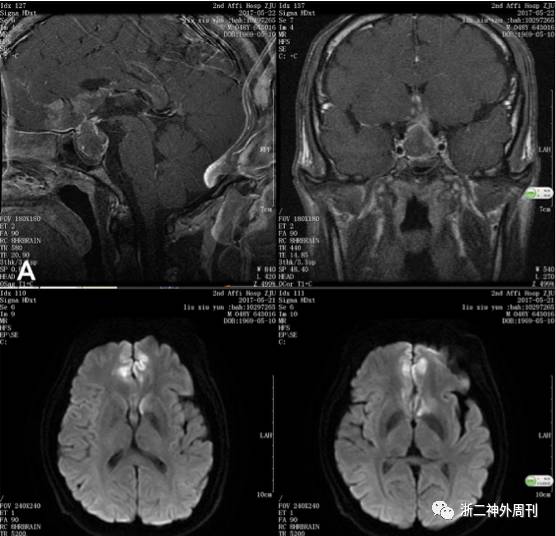

患者出院后回家,症状并无明显改善,2017.05.18日起出现头痛加重,神志淡漠,嗜睡,逐渐加重,2017.05.22再次就诊我院神经外科,查头颅CT提示蝶鞍扩大,鞍区高密度灶(图1B)。垂体磁共振增强提示鞍区占位伴出血。磁共振DWI相提示双侧额叶内侧及扣带回皮层下高信号,弥散受限,考虑急性脑梗塞(图2)。垂体激素提示:游离T3(FT3)1.74pmol/L↓、游离甲状腺素FT45.57pmol/L↓、总甲状腺素TT440.3nmol/L↓、皮质醇(8am)12.4nmol/L↓、黄体生成素<0.3IU/L↓、卵泡刺激素0.6IU/L↓。生长激素1.75ng/ml, IGF-1 79.3ng/ml↓,PRL79.3mIU/L正常。心电图提示前壁ST段抬高,肌钙蛋白-T 0.021ng/ml↑,空腹血糖14.0mmol/l↑,早餐后血糖16.2mmol/l↑。急诊拟“垂体腺瘤卒中,额叶梗塞,糖尿病”收住入院。

图2. A. 垂体增强磁共振提示鞍区占位,考虑垂体大腺瘤,伴双侧额底片状强化;B. DWI序列提示双侧额叶底部内侧,扣带回前部皮层和皮层下弥散受限,提示脑梗塞急性期。